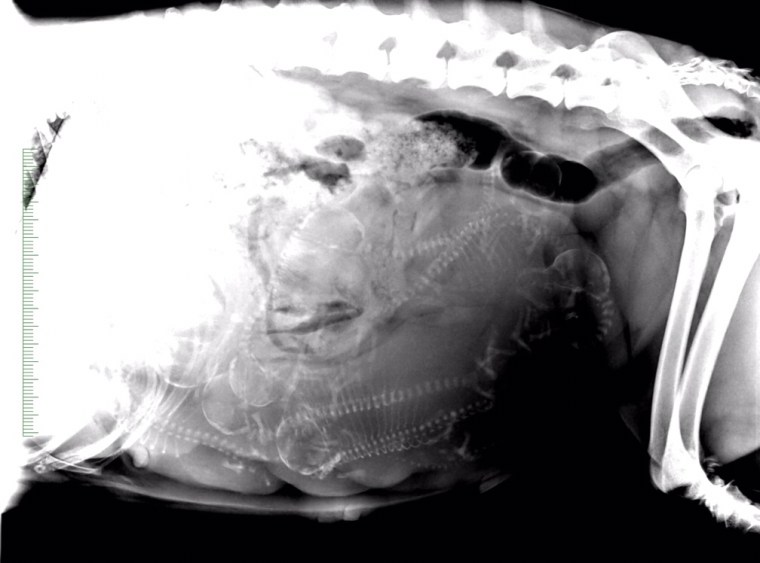

Delade med mig av den här på Facebooksidan och instagram men missade att lägga ut den här. Förra veckan åkte Aron med Prima till veterinären för en röntgen. Tyvärr fick vi inte speciellt bra bilder. Men minst 7 kunde de räkna till. Vi får se om det är alla eller om det gömmer sig någon mer därinne…

De stökar för fullt i magen och nu känner man tydliga rörelser.

En vecka kvar…